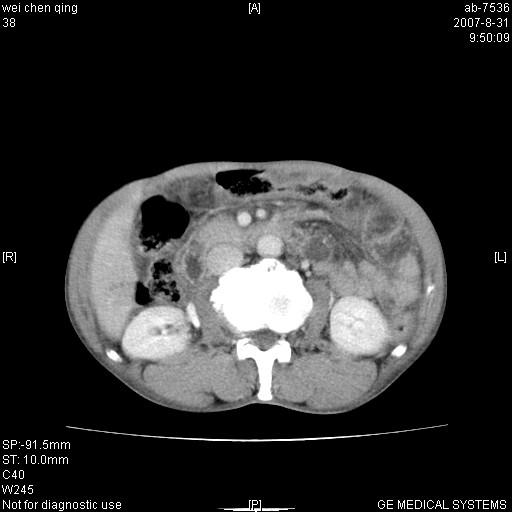

以下是引用zyyzzy在2007-8-31 14:34:00的发言:[br]该病人肝内胆管扩张,胆囊及胆总管未见明显扩张。在倒数第9层图像上可看到左右肝管结合部(肝总管)有软组织影,此处应薄层扫描。考虑肝总管占位(ca)、腹水。[br]